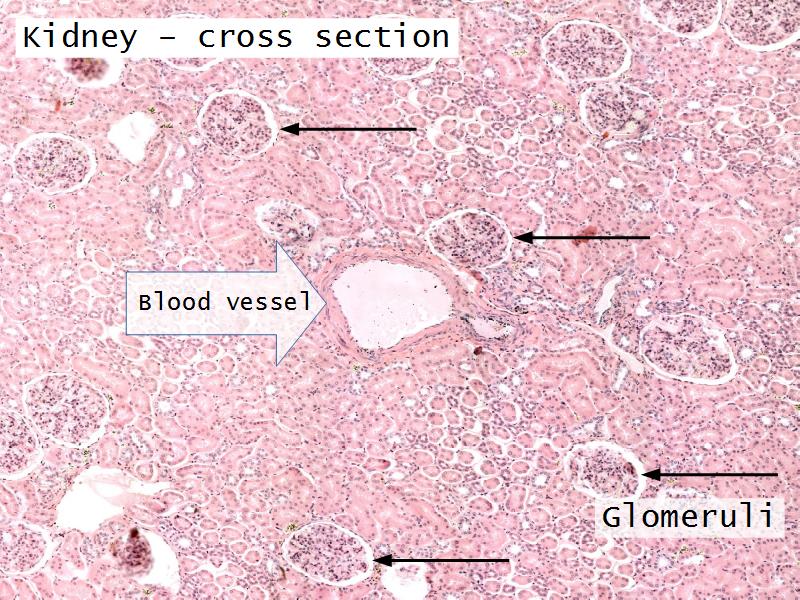

- Slide 76: Kidney